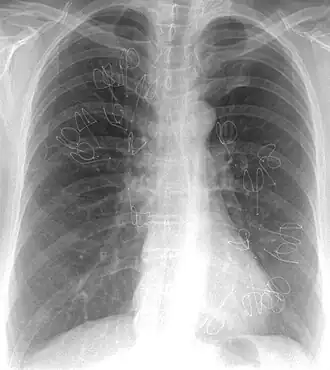

Im Röntgenbild (Röntgen-Thorax) zeigt sich das Lungenemphysem in einer verminderten Dichte des Lungengewebes. Zudem kann ein Tropfenherz ausgebildet sein.